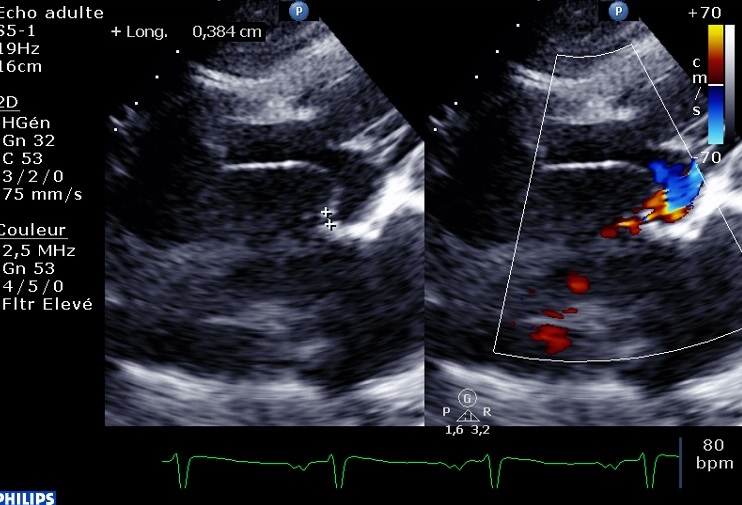

En sous costal, on devine déjà un foramen ovale perméable, mais il n’y a pas de flux décelé à l’état basal :